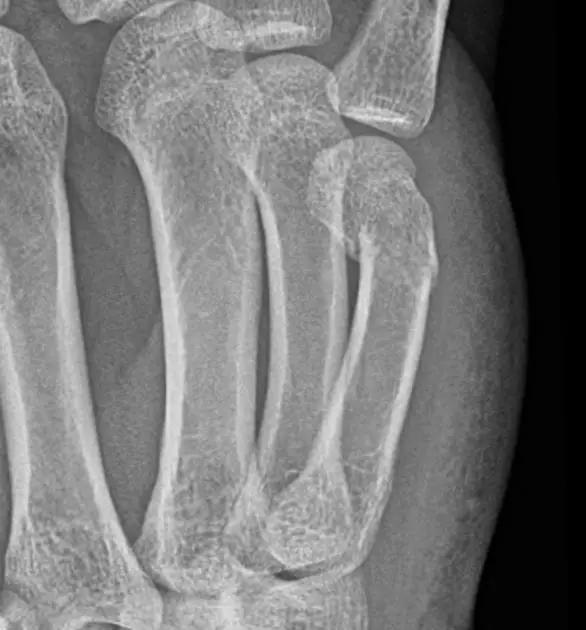

14.第五跖骨骨折

第五跖骨基底部骨折的不同类型:Stress 骨折;Jones 骨折:第五跖骨基底部以远 1 英寸内的骨折称为 Jones 骨折; Avulsion 骨折。

(来源:Radiopaedia)

Jones 骨折正位片(来源:Radiopaedia)

Jones 骨折斜位片(来源:Radiopaedia)

第五跖骨骨折还有 dancer’s fracture。